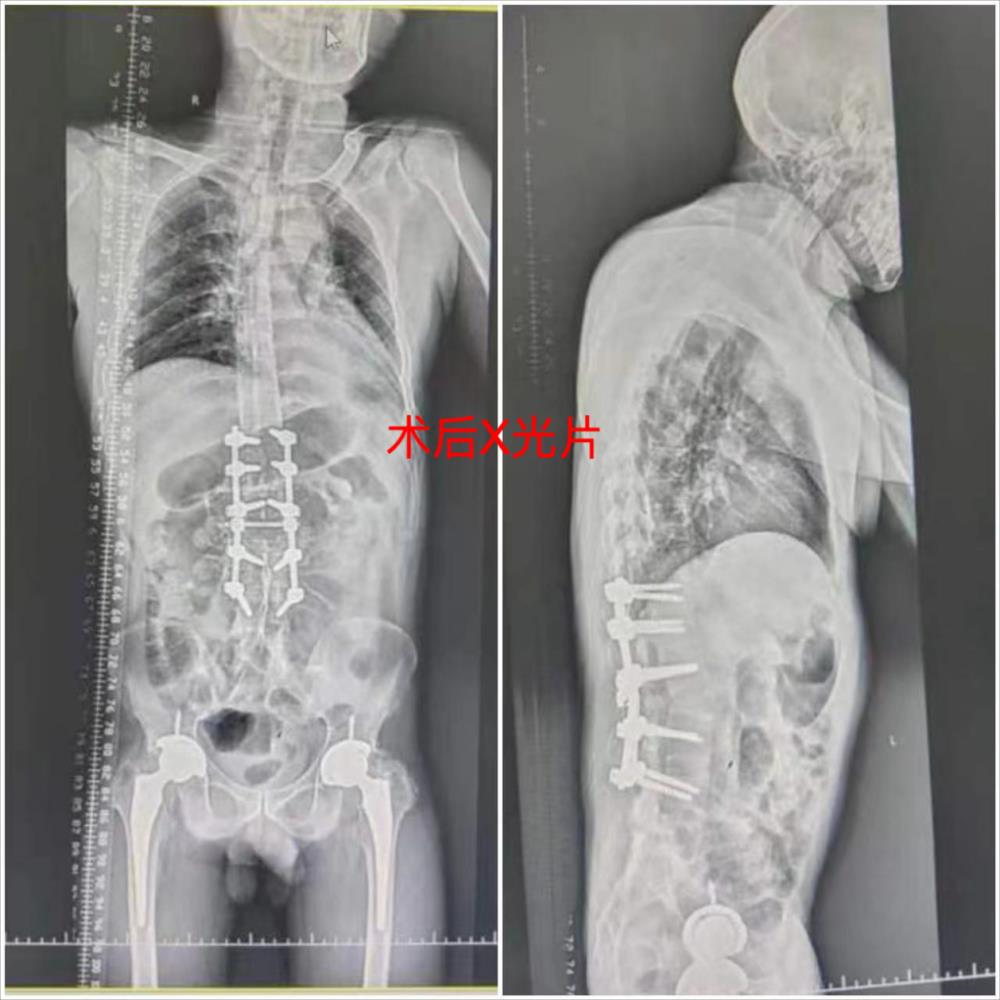

经过3天的认真准备,邹焕汶主任手术团队为其制定了最佳的治疗方案。11月3日在邹焕汶主任、谢新景副主任的主刀下历经2个小时,终于顺利完成了强直性脊柱炎并后凸畸形切开截骨矫形、减压、植骨融合内固定术,术后谭先生安全返回病房。

术后谭先生在脊柱一科医护团队精心的治疗和护理下,恢复得很快。疾病是冰冷的,但护理是有温度的。脊柱一科的护理团队通过多个措施提升优质护理工作内涵。护士为谭先生宣教手术后注意事项、指导术后健康指导和功能锻炼等科普知识,使患者和家属充分认识其重要性,消除顾虑,积极的进行运动锻炼。责任护士每日关注患者的需求,积极主动地帮助解决问题,变常规护理为个性化护理。谭先生术后出现腹胀情况,责任护士遵医嘱予腕踝针、莱服子场效应等中医特色疗法,取得良好的效果。谭先生术后腰背部情况得到了明显的改善,晚上睡觉也能平躺了,行走步态明显稳健,开始挺直了腰杆重新开始新的人生。